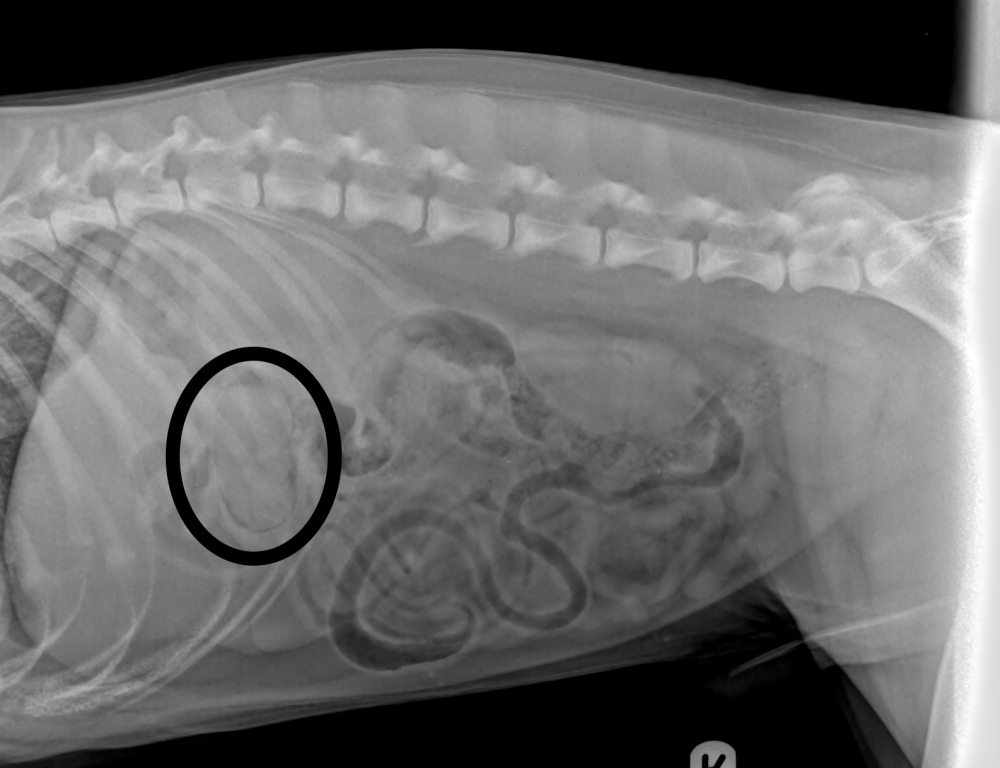

Alpha was initially rushed as an emergency to LVS’s sister practice Village Vet Hampstead, where x-rays revealed the foreign object embedded in his stomach.

“Alpha’s surgery was performed via a camera and keyhole approach. The whole mango stone was embedded into the stomach wall, which explains why the two endoscopic procedures were so tricky.